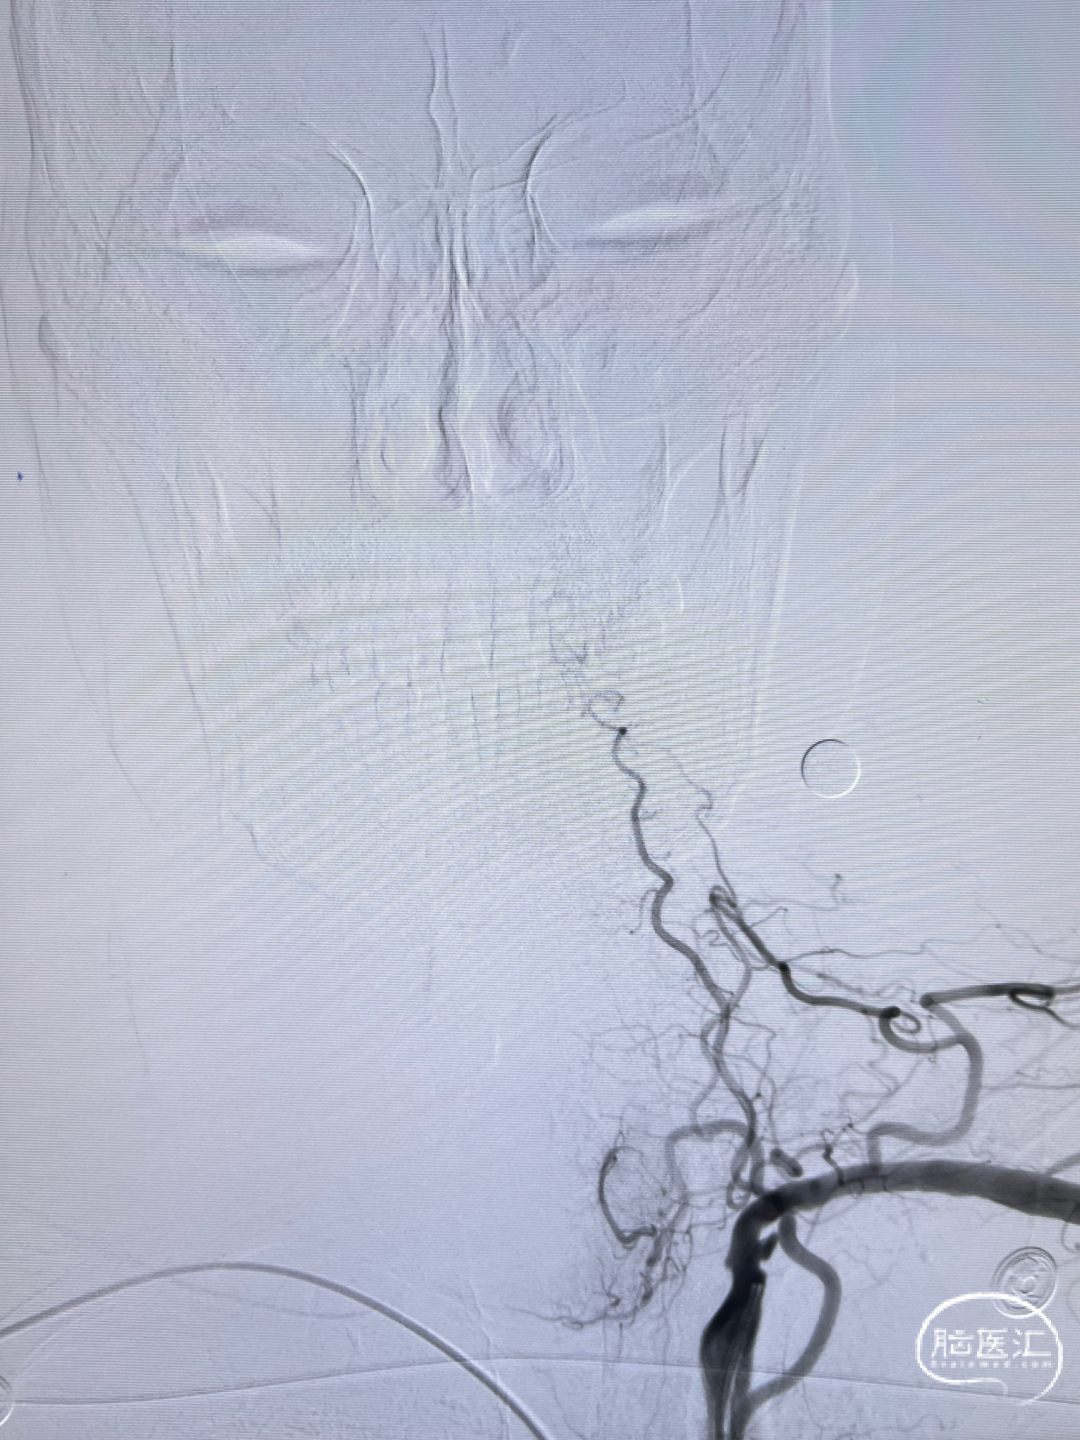

双侧股动脉造影:双侧髂动脉支架迂曲,不能通过造影导管及导丝。

经桡入路完成全脑血管造影:主动脉弓。

右侧颈内动脉闭塞。

左侧颈内动脉重度狭窄,左侧大脑中动脉闭塞,通过前交通动脉向右侧大脑中动脉供血区代偿。

后循环造影。